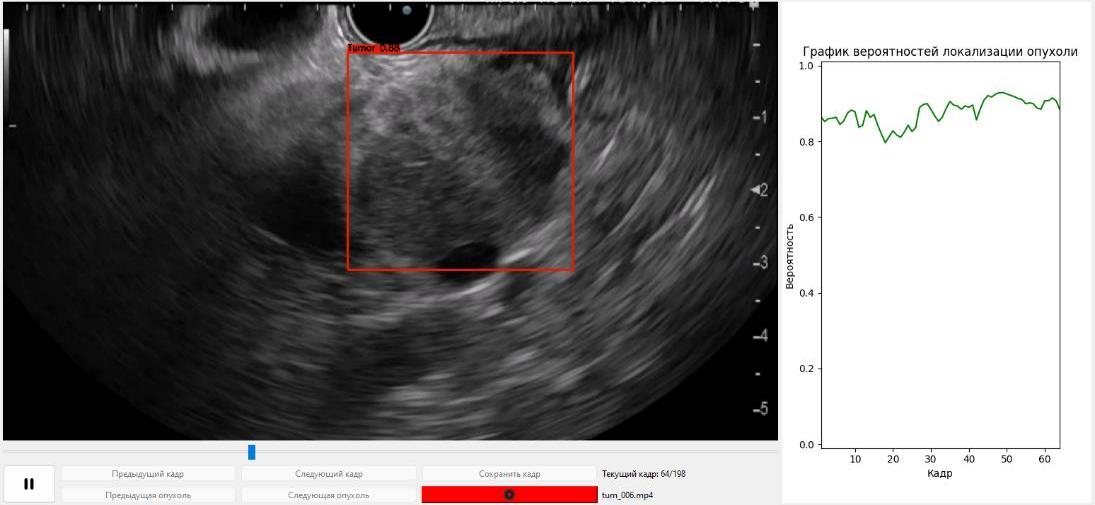

Разработано медицинское изделие «Программа ЭВМ на основе искусственного интеллекта для повышения точности диагностики рака шейки матки». Выполнена валидация конечного программного продукта (Нейросетевой алгоритм), созданного для ранней диагностики рака шейки матки в клинических условиях. Проведен сбор параметров о чувствительности (81%) и специфичности (86%), площадь под кривой (89%) метода, отладка, повторные повторяющиеся тренировки нейронной сети с учетом ранее распознанных ошибочных распознаваний. С целью регистрации разработанной программы ЭВМ как медицинского изделия, успешно пройдены технические и клинические испытания.

В 2024 году на основе обучения сверточной нейронной сети, получена модель детекции солидных новообразований поджелудочной железы при ЭУС, которая положена в основу программы для ЭВМ. При использовании дополнительного датасета проведено тестирование и отладка параметров модели и функций компьютерной программы. Параметры работы программы доведены до оптимальных (чувствительность – 91%, специфичность — 84%). С целью регистрации программы как медицинского изделия успешно пройдены технические и клинические испытания, и регистрационное досье подано в Росздравнадзор.